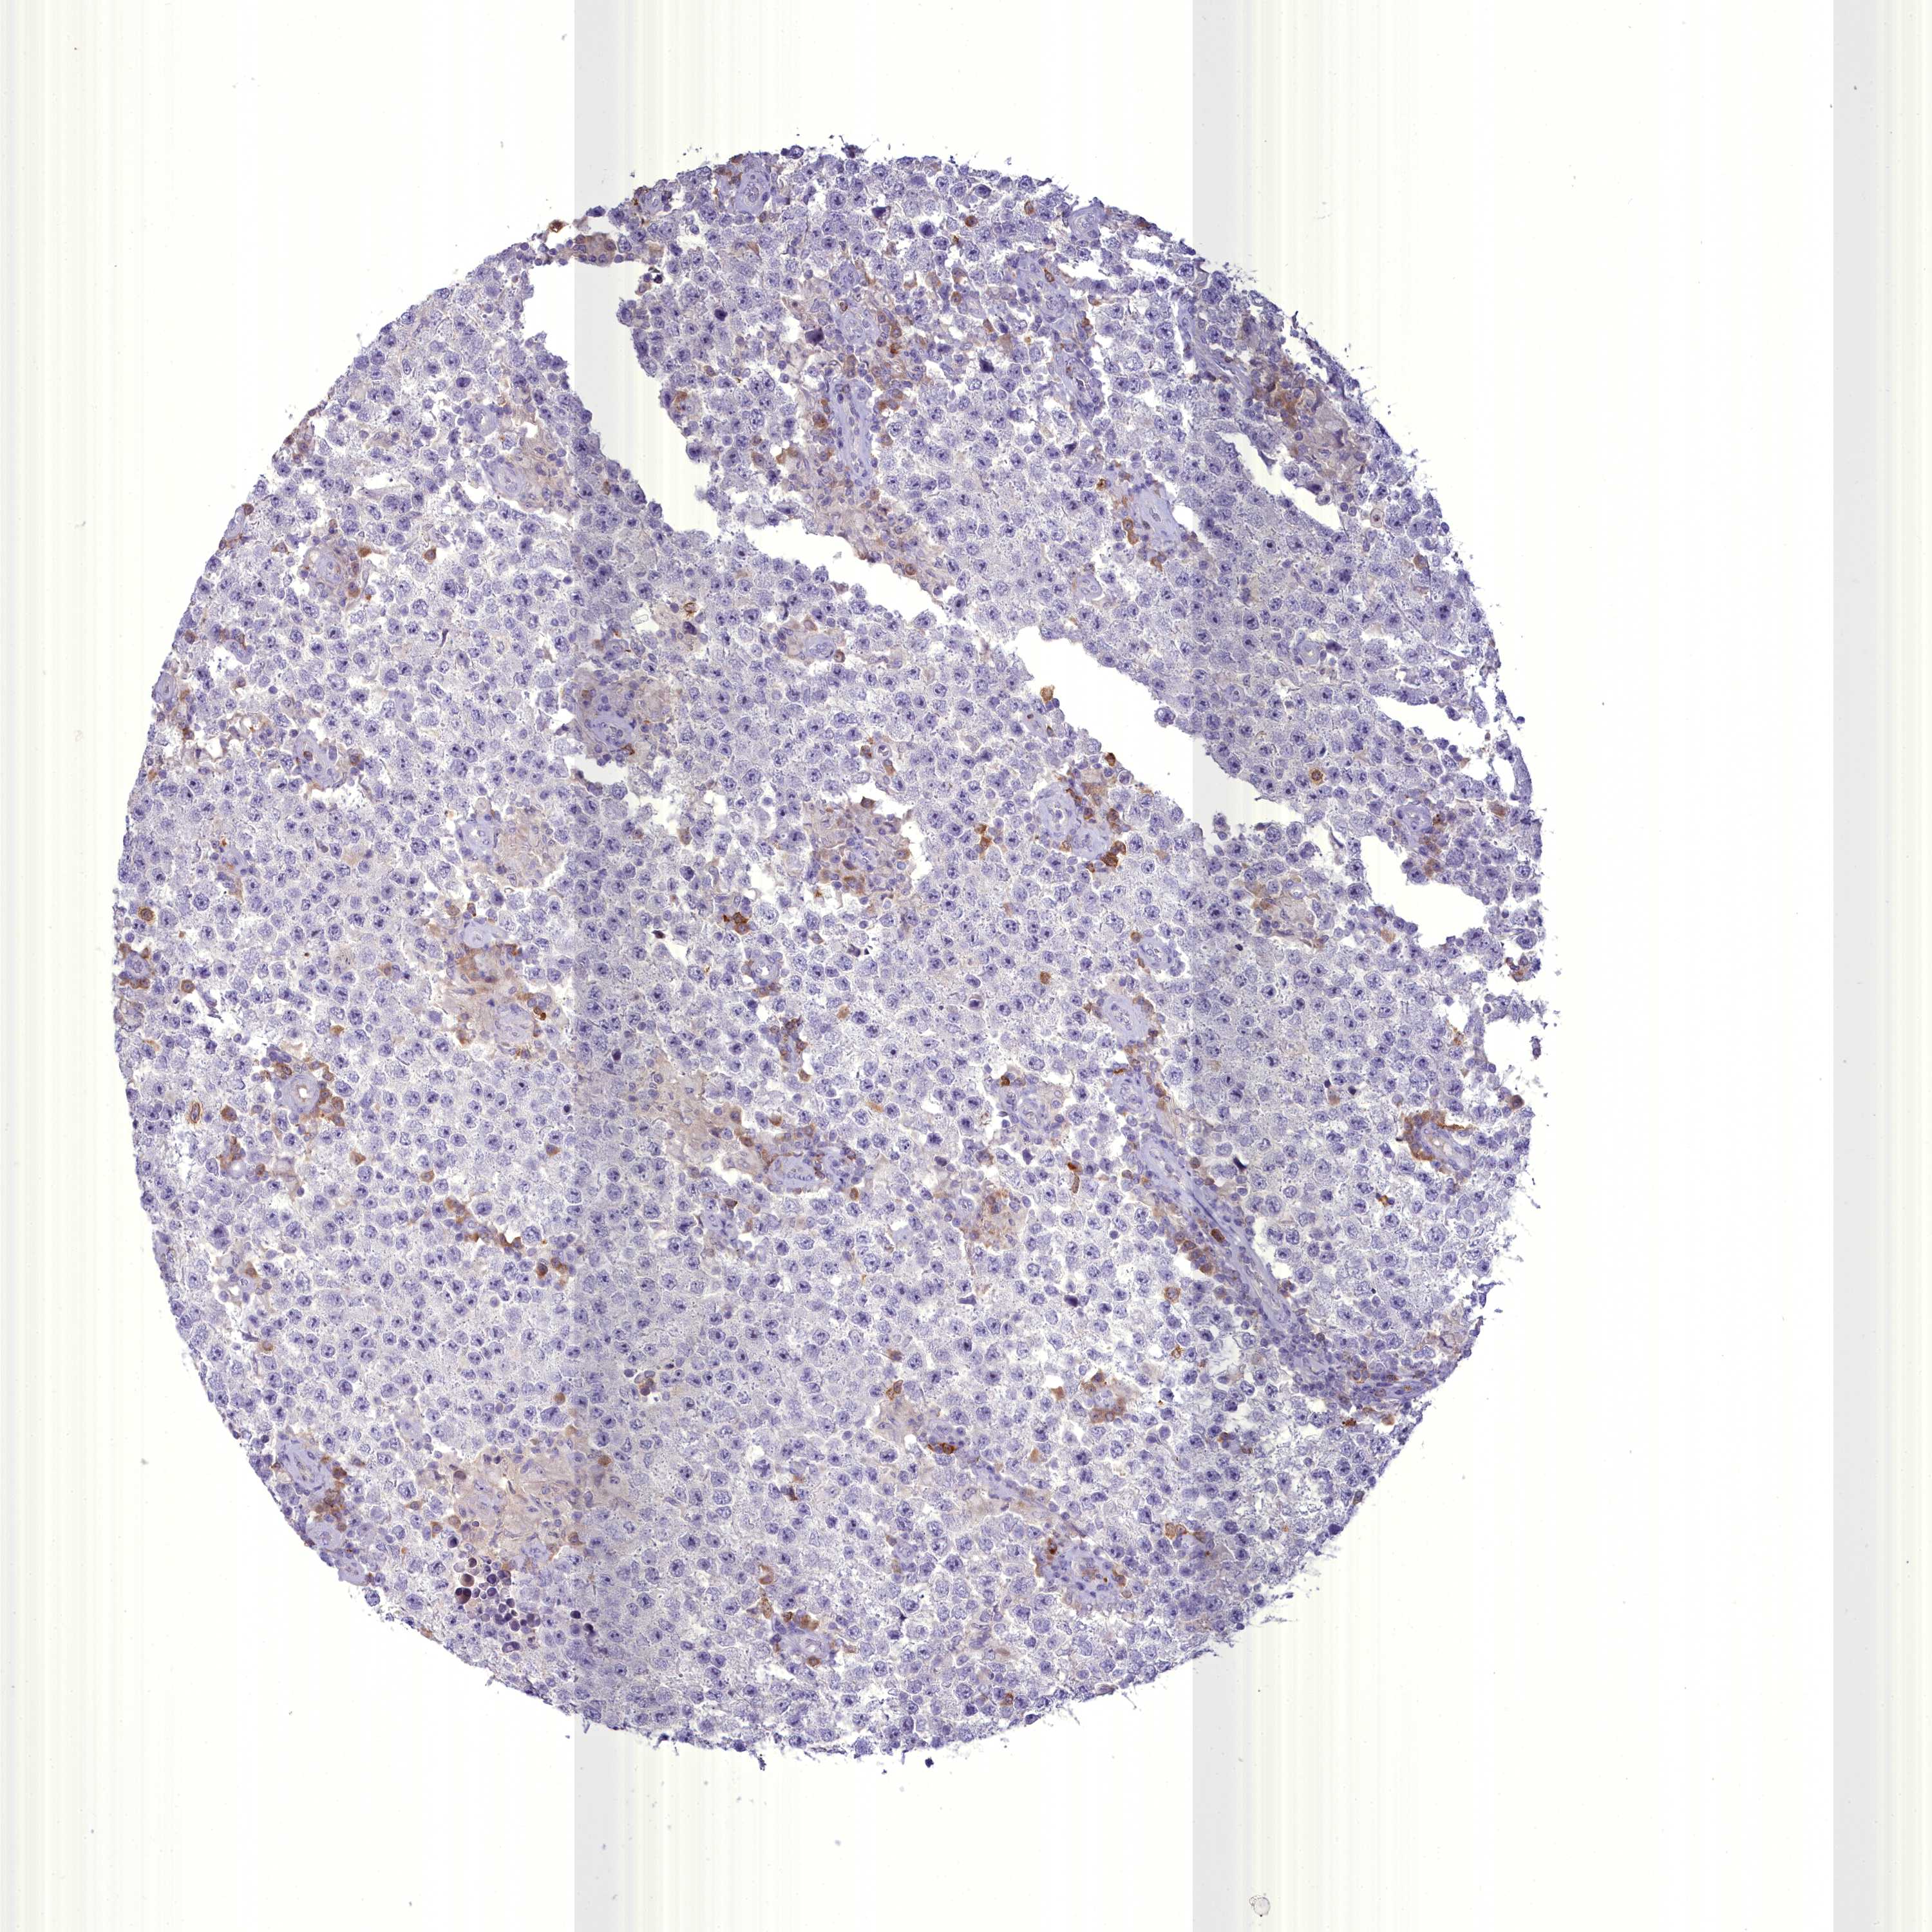

TESTIS CANCER - Protein expressioni

A mouse-over function shows sample information and annotation data. Click on an image to view it in a full screen mode. Samples can be filtered based on level of antibody staining by selecting one or several of the following categories: high, medium, low and not detected. The assay and annotation is described here.

Note that samples used for immunohistochemistry by the Human Protein Atlas do not correspond to samples in the TCGA dataset.

Antibody stainingi

Antibody staining in the annotated cell types in the current human tissue is reported as not detected, low, medium, or high, based on conventional immunohistochemistry profiling in selected tissues. This score is based on the combination of the staining intensity and fraction of stained cells.

Each image is clickable and will lead to virtual microscopy that enables deeper exploration of all samples and also displays staining intensity scores, fraction scores and subcellular localization as well as patient and tissue information for each sample.

Antibody HPA038309

Carcinoma, Embryonal, NOS

Seminoma, NOS